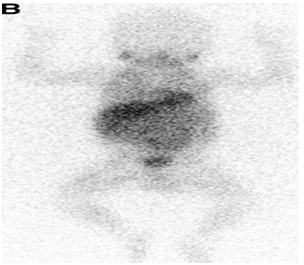

14month old female with a history of stage III neuroblastoma, no other comorbidities, presented to our institution for a left thoracoabdominal exploration and resection. As the surgeon made preparations to close, the patient’s SBP’s almost immediately decreased from 90’s (general trend) to 60’s mmHg, accompanied by an elevation in heart rate. Several 20 cc/kg boluses of isotonic crystalloid fluid were administered with no change in hemodynamics. A dopamine infusion was started for refractory hypotension. Surgical exploration revealed the small bowel to be diffusely dusky and ischemic; the surgeon identified a thrombus in the superior mesenteric artery (SMA) (Figure 2 & 3).1˗3 An ABG returned with a pH 7.047 in the setting of profound lactate acidosis with a lactate of 10.4 mmol/L. Vascular surgery was consulted for an SMA embolectomy and heparin 250 units IV was given. As the case progressed, dopamine was up-titrated to maintain MAPs > 40mmHg. The patient’s lactate continued to rise in spite of reperfusion to the SMA, leading to significant vasoplegia and requiring the addition of an epinephrine infusion. A Whipple procedure was performed and the patient was closed, left in discontinuity. She was transported to the PICU intubated, on dopamine and epinephrine infusions.

Figure 2 I-MIBG scan.1-3